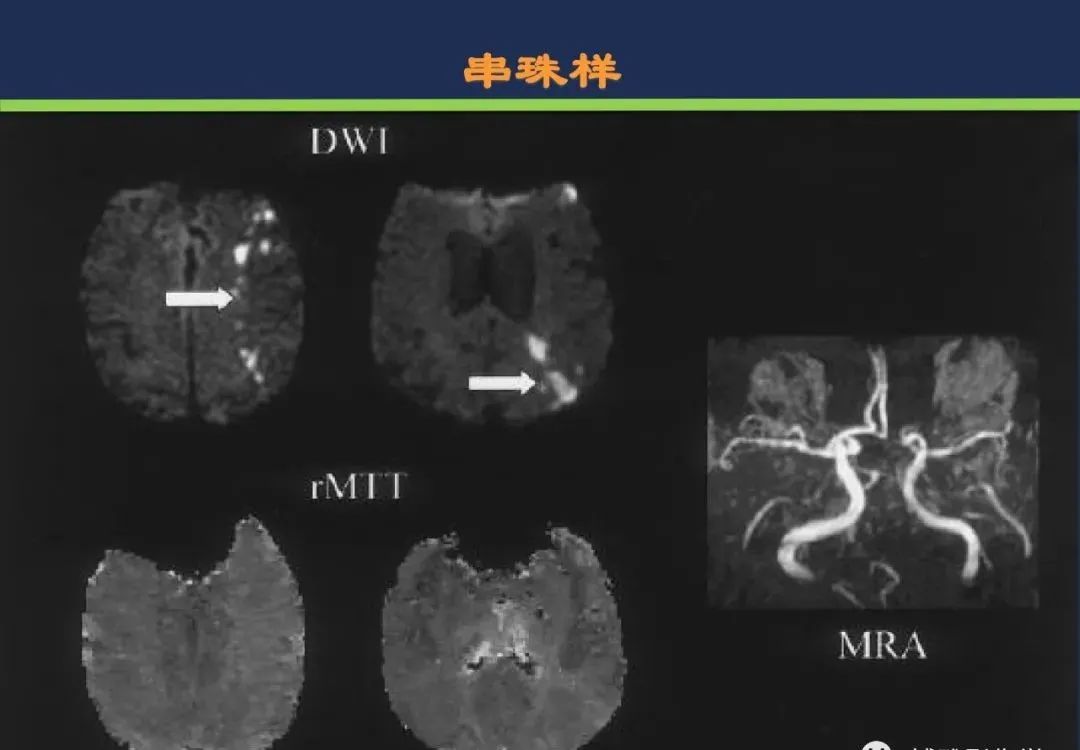

颈内动脉系统梗死颈内动脉大脑中动脉